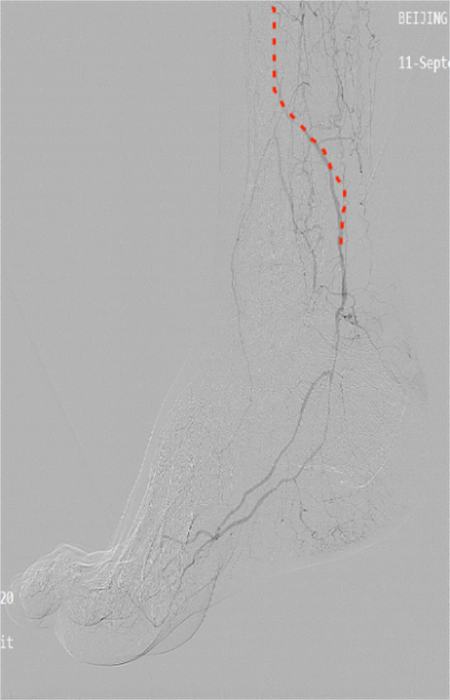

此次手術(shù)針對患者的下肢動脈粥樣硬化閉塞癥和糖尿病足周圍血管病變,預(yù)開通血管,使因血運不足引起的潰瘍愈合。(紅色虛線標(biāo)注為狹窄閉塞的血管)

團(tuán)隊?wèi){借精準(zhǔn)的術(shù)前評估、規(guī)范的手術(shù)操作,成功為患者開通直達(dá)創(chuàng)面血管,改善創(chuàng)面供血。